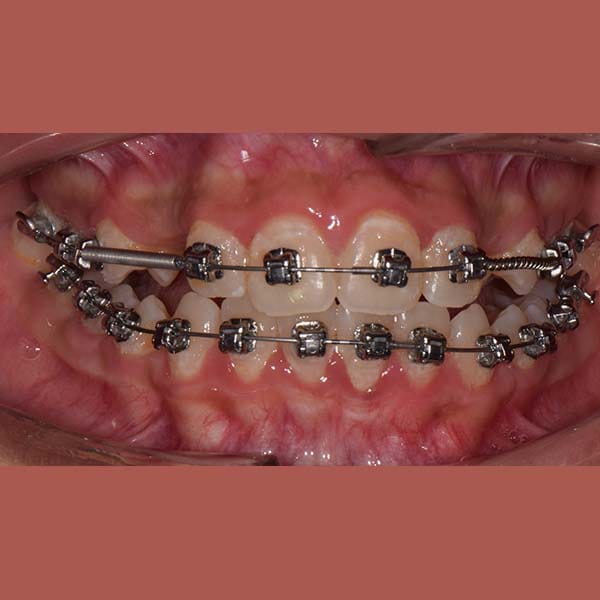

We have treated her by means of Daimon braces without any tooth extraction and opened a space for the buried canine to stand in its proper position. In the end, our little friend gained a wide and beautiful smile.